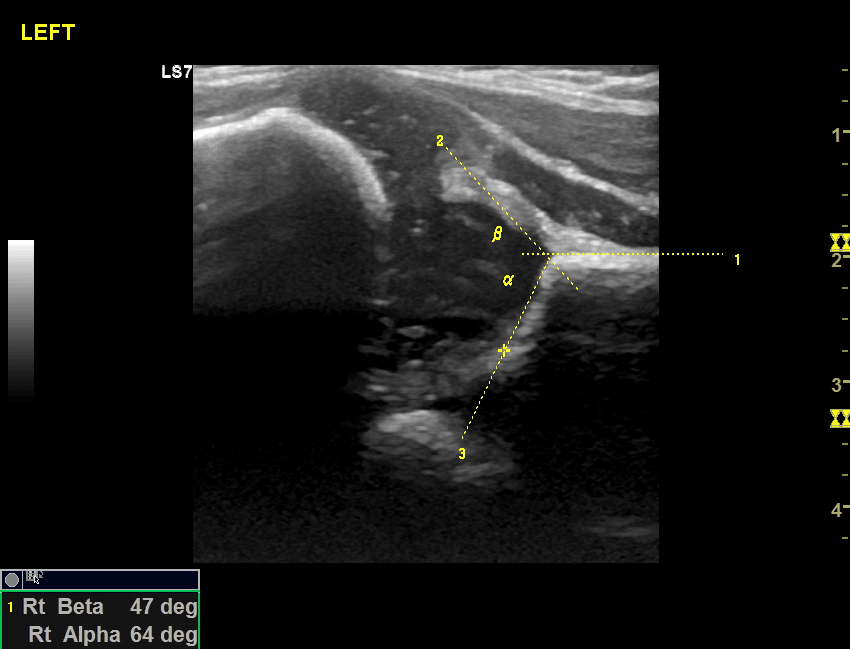

To 1992 H Rosendahl πρότεινε το συνδυασμό των 2 επικρατέστερων μεθόδων ( μέθοδος Graf και μέθοδος Harcke )τη γνωστή σήμερα μέθοδο Rosendahl ή αλλιώς τροποποιημένη μέθοδος Graf( (modified -Graf method) η οποία από το 2011 με βάση τις κατευθυντήριες οδηγίες της Ευρωπαϊκής Παιδοακτινολογικής Εταιρίας (ESPR) είναι η προτεινόμενη μέθοδος εξέτασης. Η Rosendahl και ο Graf είναι πολύ αυστηροί στην μεθοδολογία της εξέτασης και ιδιαίτερα στη σωστή λήψη των υπερηχογραφικών εικόνων ώστε να αποφευχθούν τυχόν λάθη. Η μέτρηση των γωνιών κατά Graf προϋποθέτει να περιλαμβάνονται στην εικόνα όλα τα ανατομικά στοιχεία της άρθρωσης και οι 3 γραμμές να διέρχονται με ακρίβεια από τα σωστά σημεία.

Έτσι μόνο στην τέλεια άρθρωση οι 3 γραμμές εφάπτονται στο ίδιο σημείο, εύρημα όχι συχνό και όχι υποχρεωτικά αναμενόμενο στη φυσιολογική άρθρωση !! Αντίστοιχα η δυναμική εξέταση χρήζει ιδιαίτερης προσοχής για να αποφευχθούν τυχόν λάθη και να μην «ταλαιπωρείται» το βρέφος με συχνές –άσκοπες επαναλήψεις.